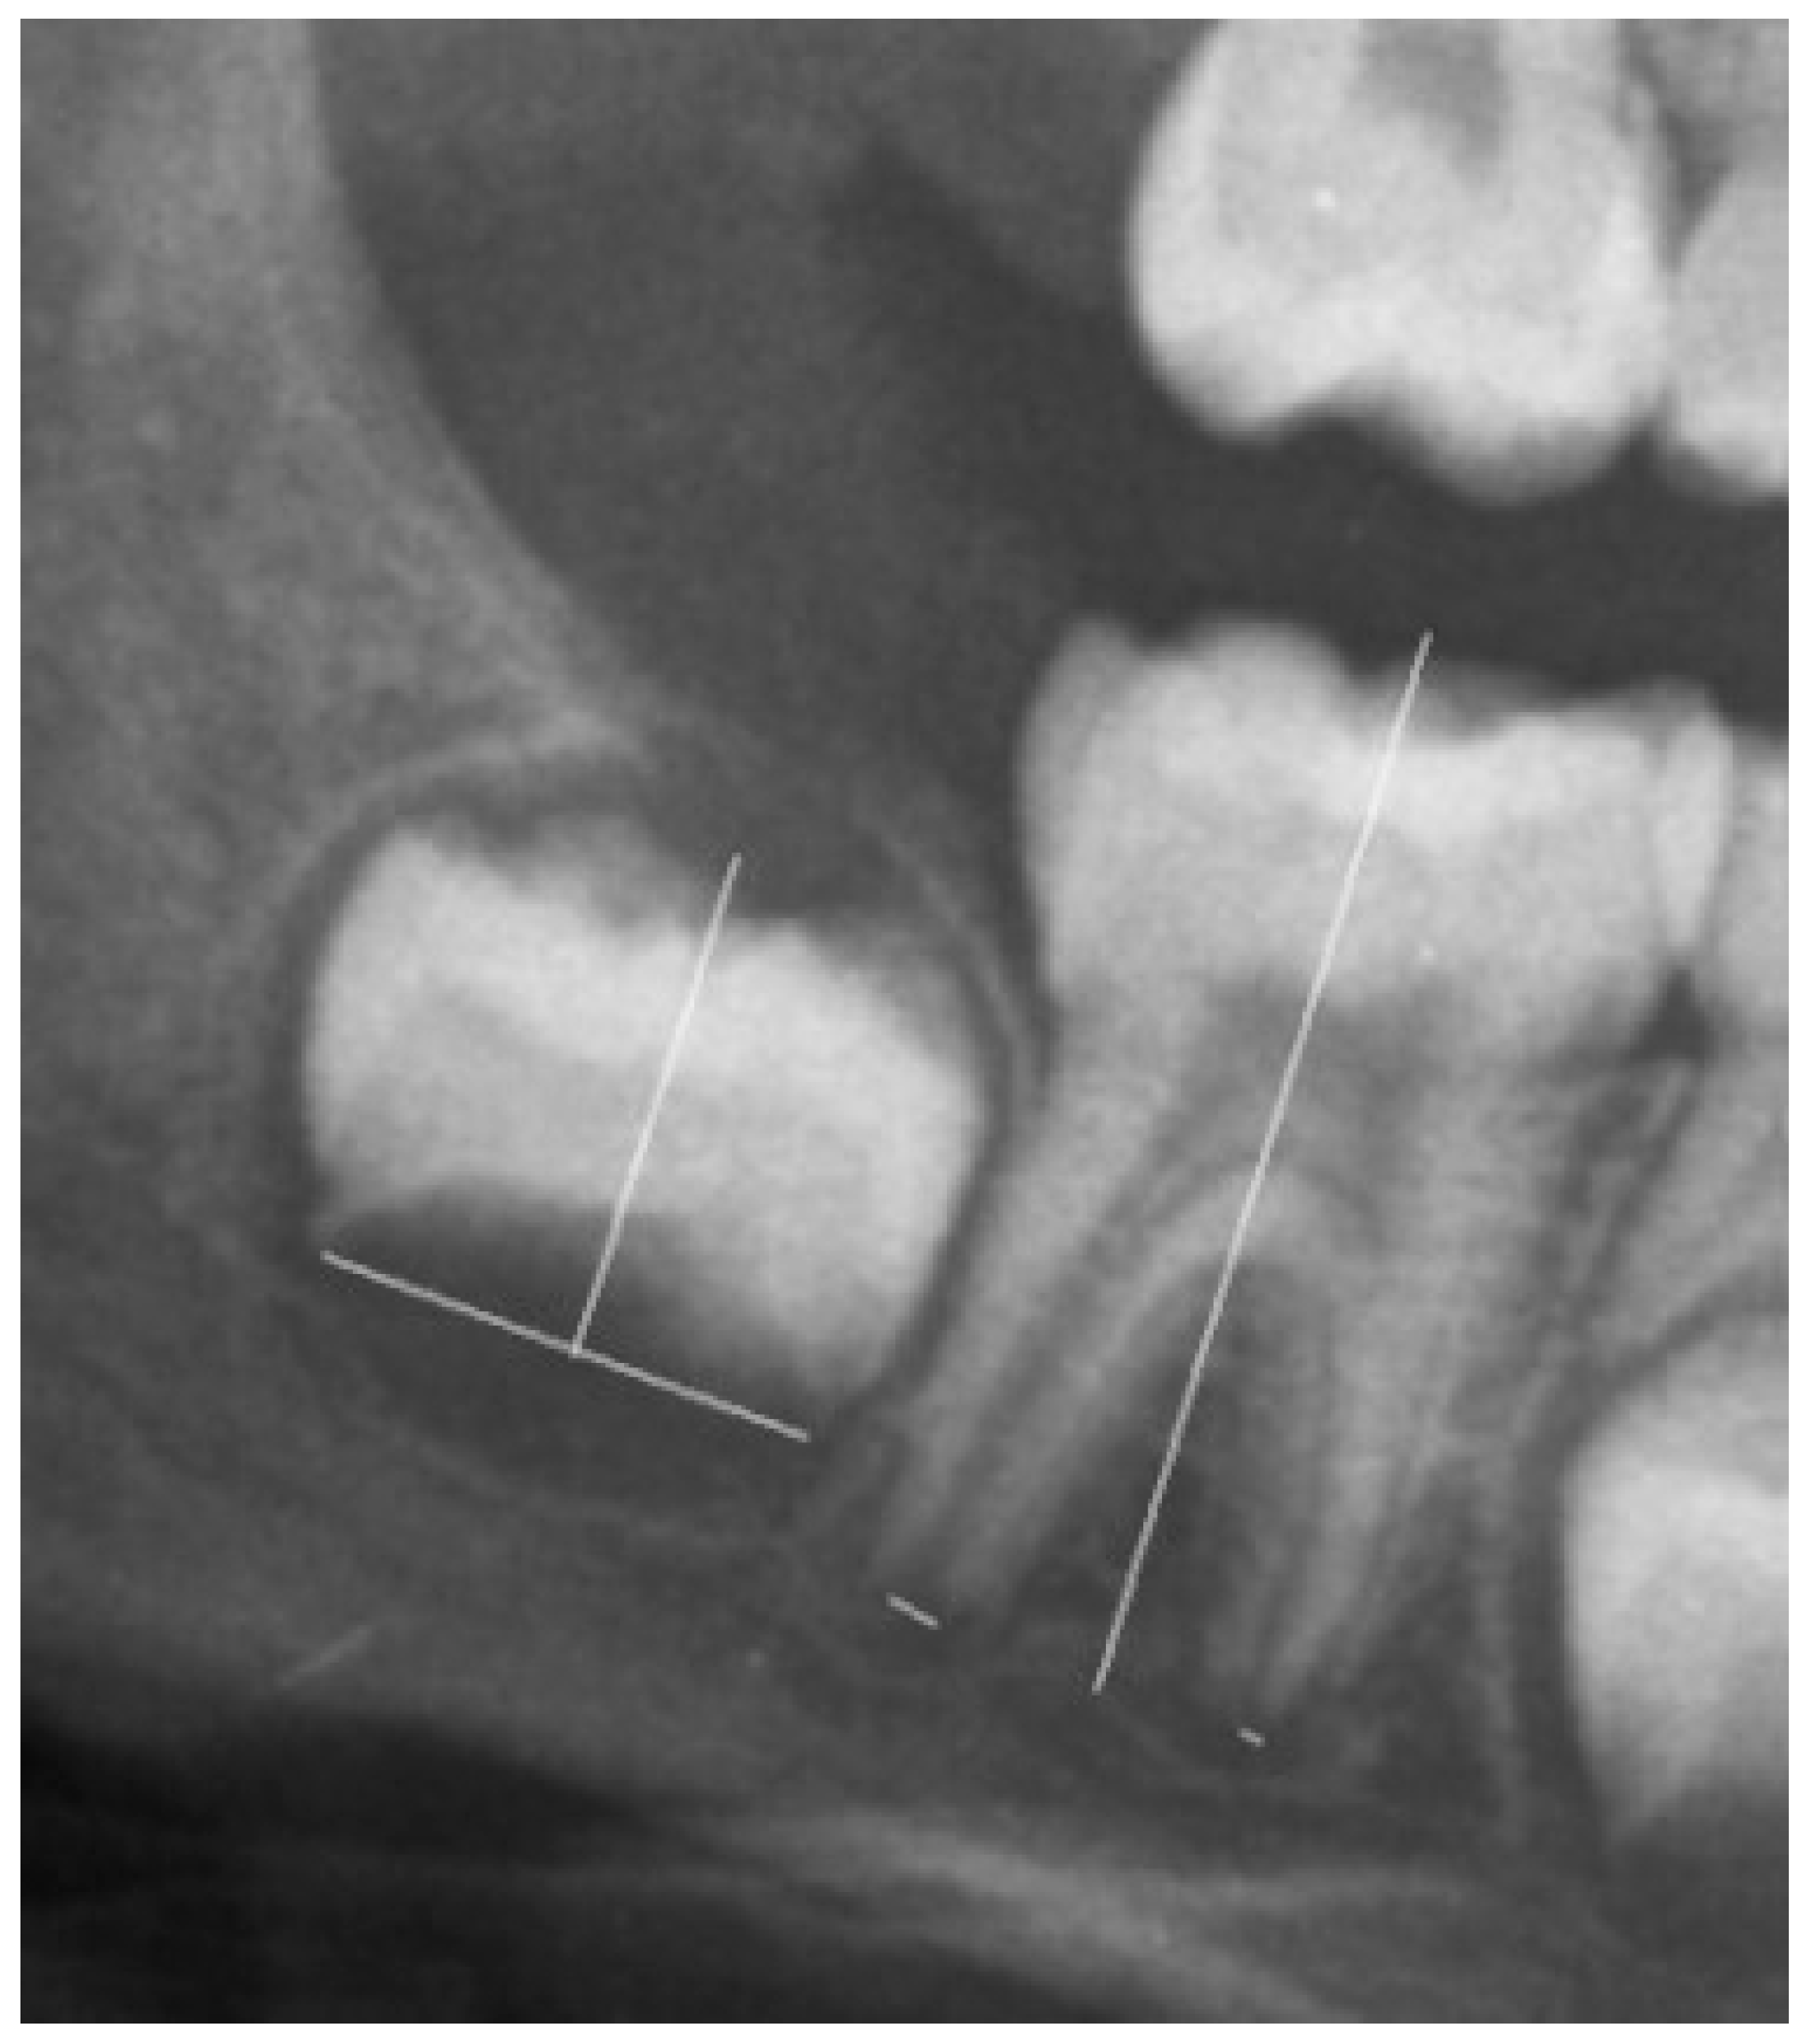

Clinical data were used to detect the best cut-off for 14 years of age. The data used for the survey were processed anonymously and collected by healthcare professionals with prior informed consent, in compliance with laws on confidentiality and protection of personal data. If at least two permanent lower molars were not completely developed, we selected a cut-off following the study on Italian children [6]. The ratio between the distance between the inner sides of the open apex and the tooth length of seven permanent teeth of the left mandibular were measured (Figure 1) [6,7].

Age estimation was evaluated by the sum of normalized open apices and numbers (N0) of teeth with complete root development [7].

Specifically, seven left permanent mandibular teeth were assessed.

Figure 1. An example of tooth measurement with one or two roots.